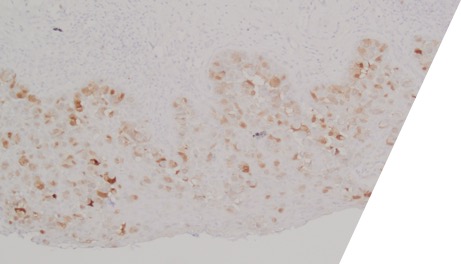

Large round malignant cells with pale cytoplasm and enlarged nucleolus and prominent nucleoli are present within the epidermis. The cytoplasm contains mucin. Differential diagnosis include HSIL, Paget disease (primary or secondary), and melanoma in situ. The lesional cells are strongly positive for CK7, CK20, CAM5.2 and GATA3, scattered positive for p63; and patchy staining for p16, negative for ER and SOX10. High-risk HPV-ISH is negative.

Patient's history of invasive high-grade urothelial carcinoma is shown. The tumor cells showed similar morphological features to the tumor cells in current specimen. The findings are compatible with secondary involvement by previously diagnosed urothelial carcinoma.